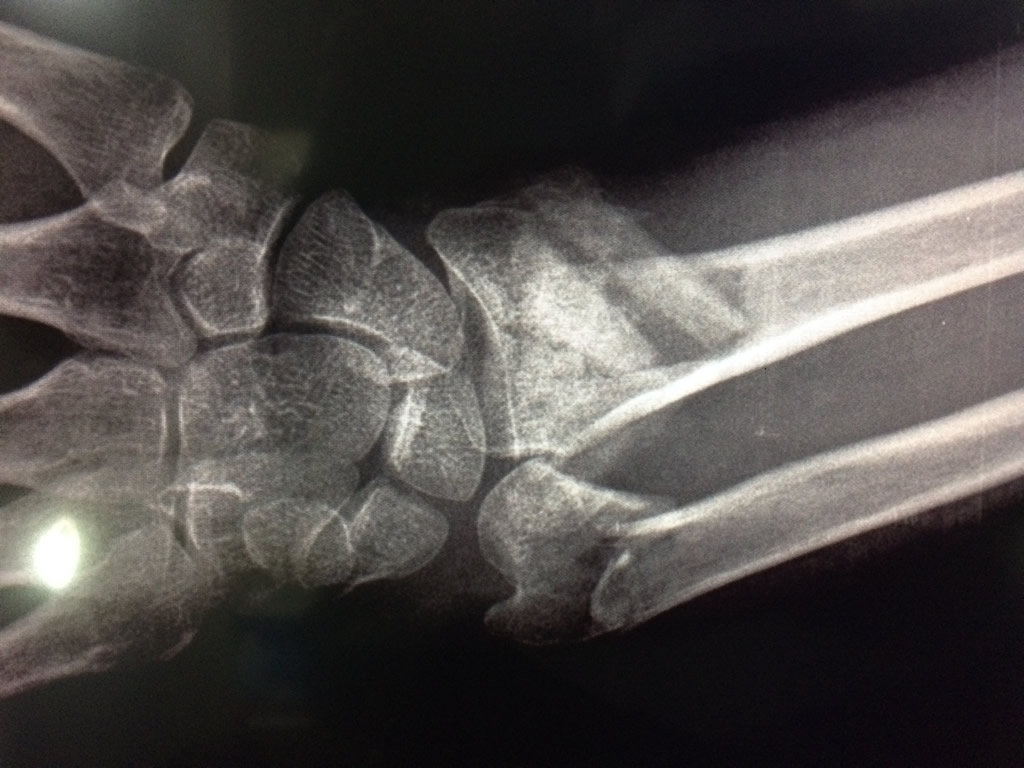

Cirugías de Calcaneo - Cirugías de Muñecas y Manos

Los procedimientos más comunes en cirugía de la mano son aquellos destinados a reparar traumatismos, incluyendo lesiones de tendones, nervios, vasos sanguíneos, y articulaciones; huesos fracturados; y quemaduras, cortes, y otros daños de la piel.